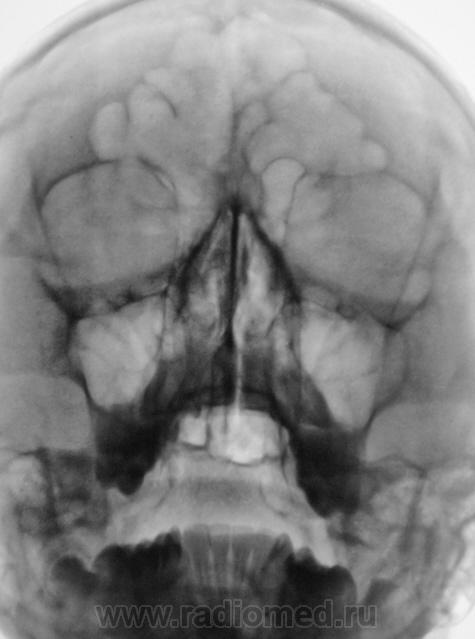

Нормальнейшая норма+игра теней.

Если были сомнения, надо было доснять носолобную проекцию.

Зеленым я обвел контуры пахухи, которая как бы наехала на тень альвеолярного отростка (синий цвет)- просто сумация теней....

Допустите вариант, что нижние края пазухи как бы охватывают альвеолярный отросток СПЕРЕДИ и СЗАДИ, вот тогда такая картинка и появится...

Я тоже вижу норму.

Неоднозначно всё